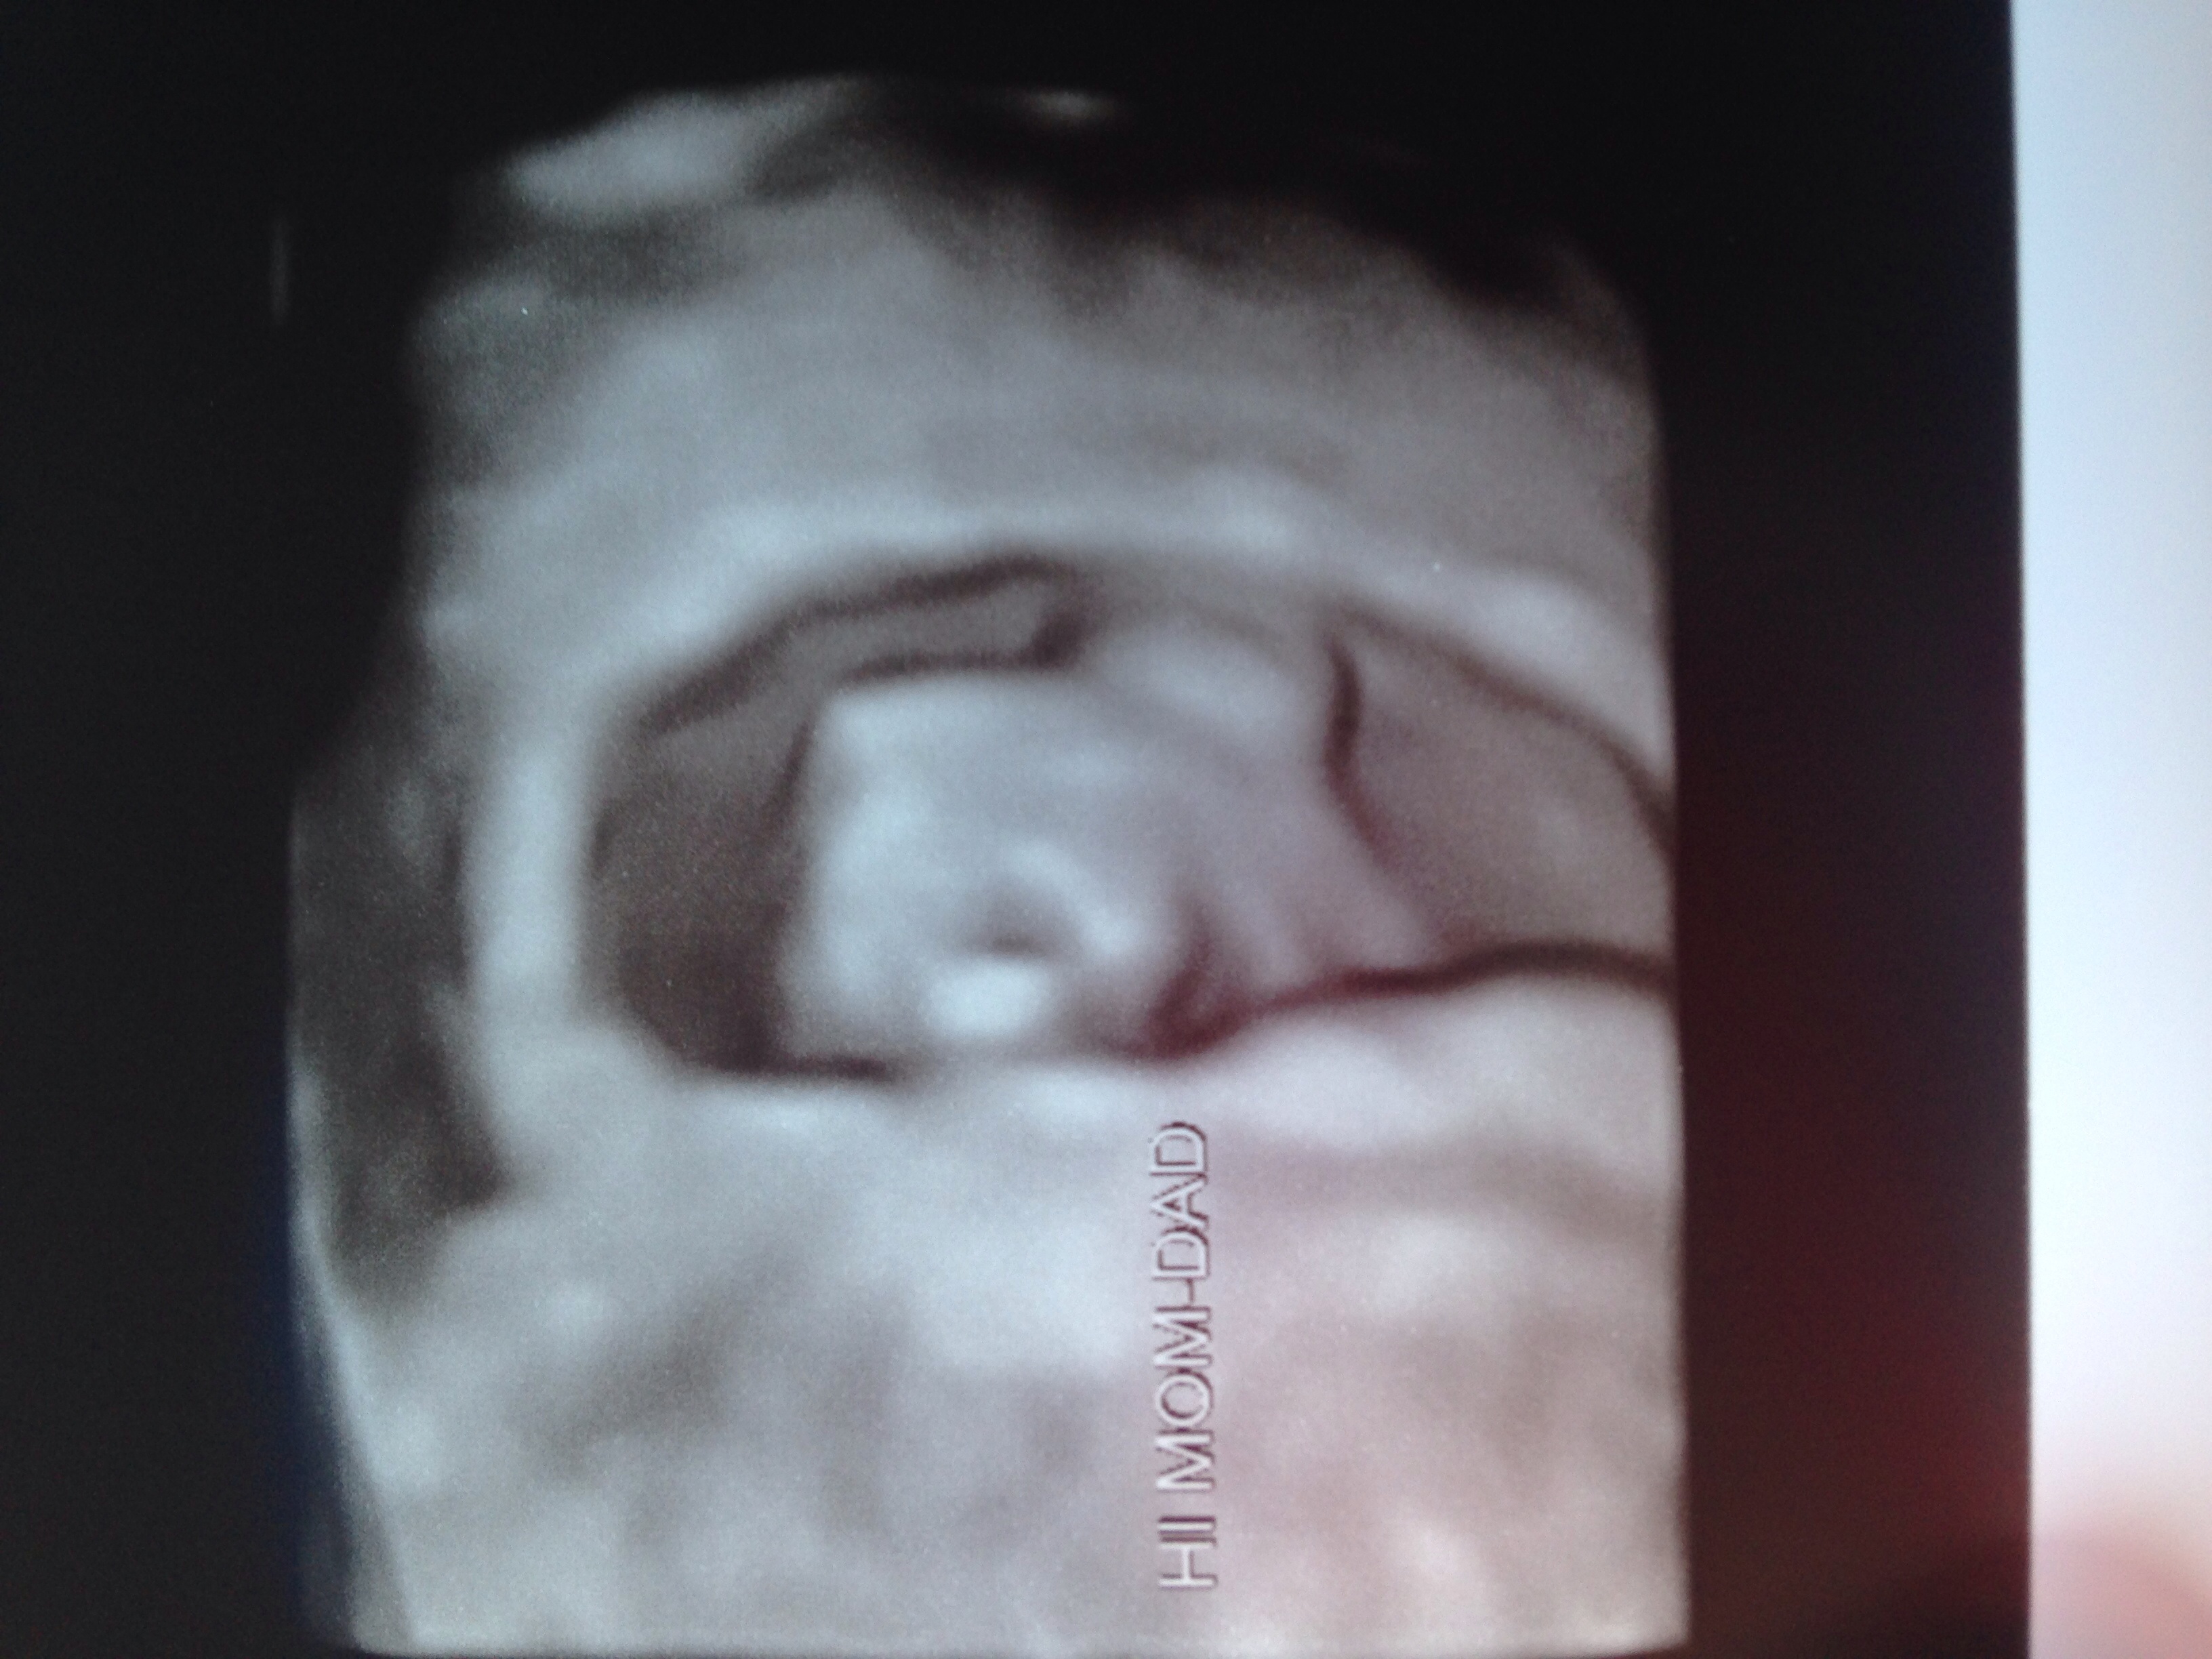

Happy Friday ladies!! I was able to take another peak at Baby Jellybean today!! Measuring right on time. FHB 165 per minute!! Doctors feel pretty confident this IS our rainbow baby!! Blessed is an understatement for me right now!! I keep all of you in my thoughts and prayers and really hope that we have a wonderful present waiting for us in early 2016!! Next ultrasound isn't for a month... But, we will be 12 weeks then and baby will look a lot more like a baby!! Yay! :-)